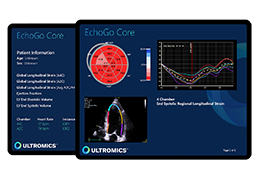

分析智能。

这些功能利用数字控制面板分析运营、业务和临床绩效。

使管理员能够跟踪关键参数,包括平均曝光率、拒绝的影像和探测器统计信息。

帮助确定需要改进的方面,支持为员工和部门制定适当的改进计划。